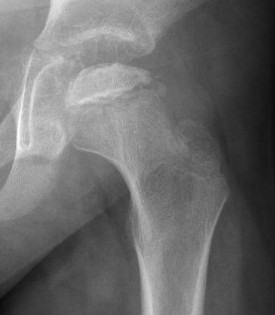

3. Reossification

Duration : 1.5 - 3 years

Pathologic Process

- starts at margins & progresses centrally

- eventually new areas coalesce & epiphysis regains normal strength & density

XRay

- Better defined shape

- Return of bone density

4. Remodelling

Duration : Occurs until skeletal maturity

Xray - May have flattening of the head and neck